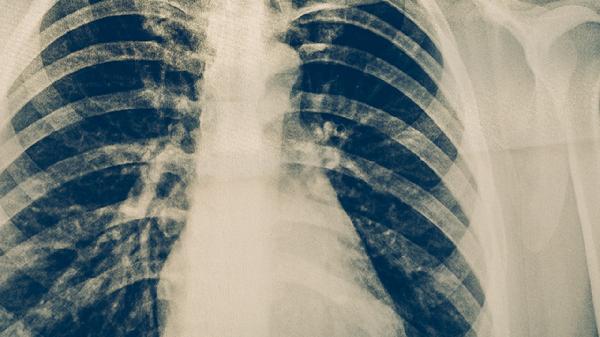

4、胃部CT检查

采用多层螺旋CT进行胃部三维成像,能清晰显示胃壁增厚、周围淋巴结肿大及肿瘤浸润深度,对评估胃癌分期具有重要价值。增强CT还可检测胃部血管异常,但难以发现表浅黏膜病变,且需注射对比剂,肾功能不全者慎用。